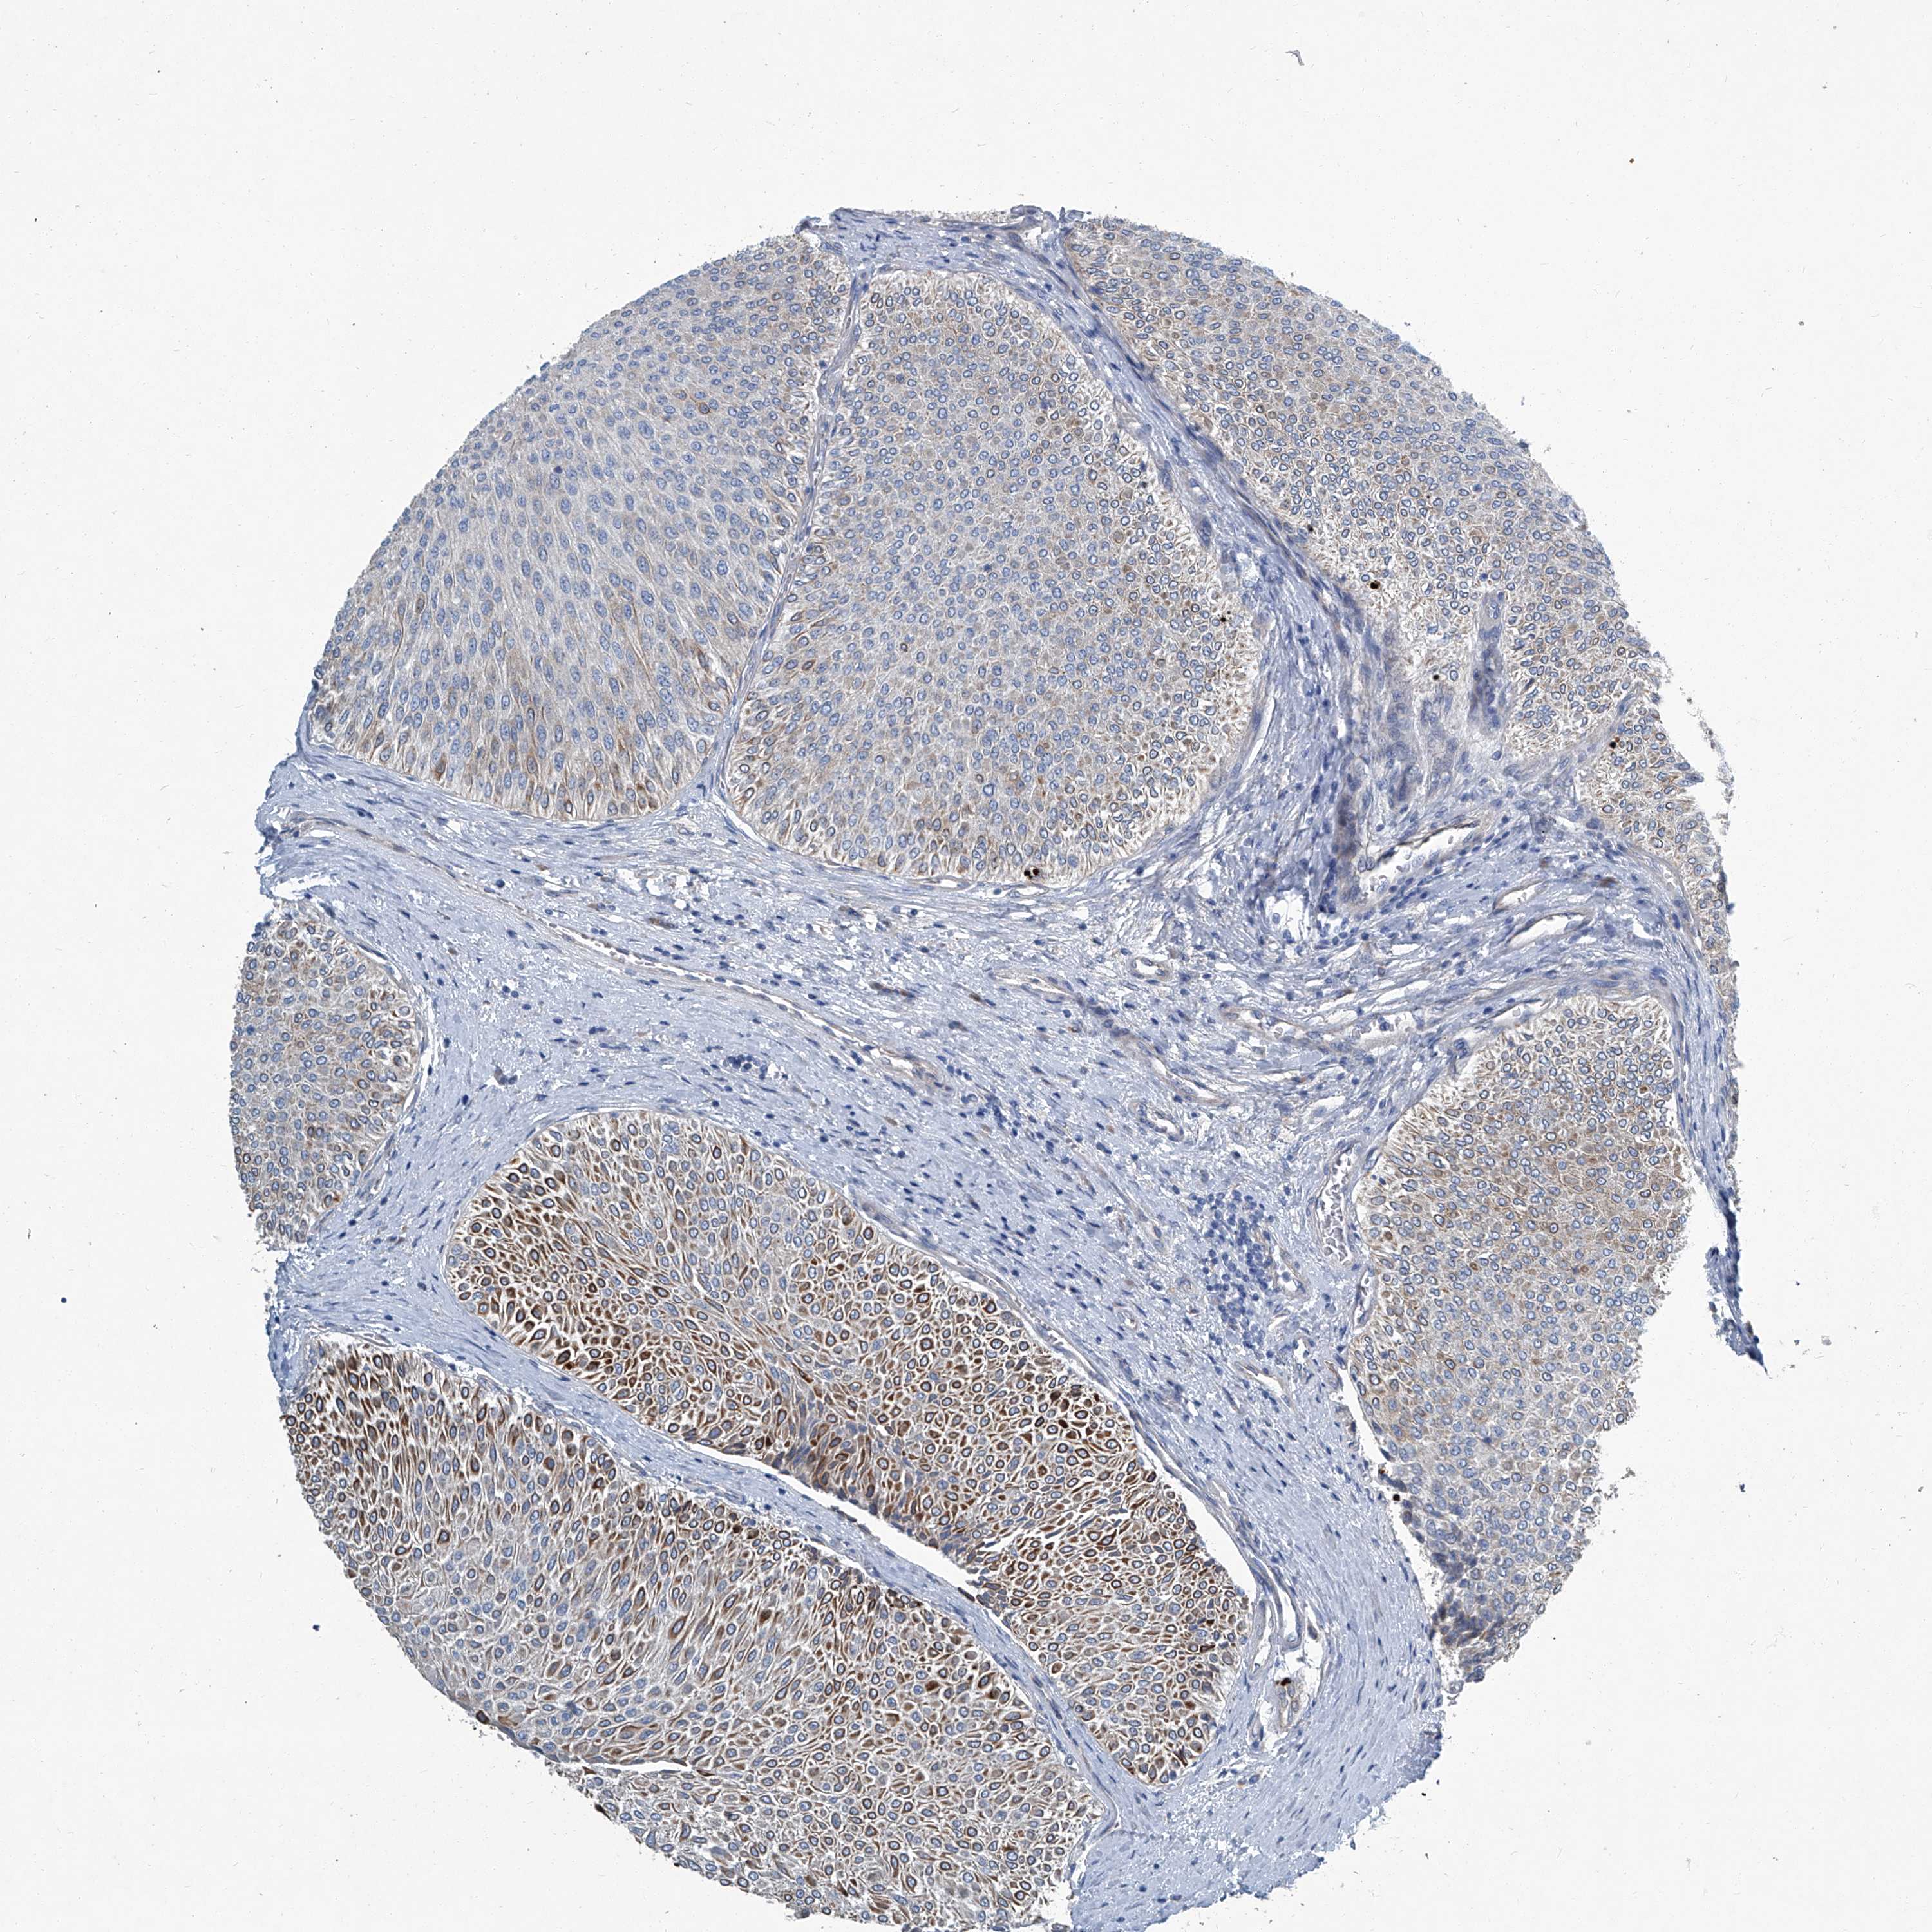

UROTHELIAL CANCER - Protein expressioni

A mouse-over function shows sample information and annotation data. Click on an image to view it in a full screen mode. Samples can be filtered based on level of antibody staining by selecting one or several of the following categories: high, medium, low and not detected. The assay and annotation is described here.

Note that samples used for immunohistochemistry by the Human Protein Atlas do not correspond to samples in the TCGA dataset.

Antibody stainingi

Antibody staining in the annotated cell types in the current human tissue is reported as not detected, low, medium, or high, based on conventional immunohistochemistry profiling in selected tissues. This score is based on the combination of the staining intensity and fraction of stained cells.

Each image is clickable and will lead to virtual microscopy that enables deeper exploration of all samples and also displays staining intensity scores, fraction scores and subcellular localization as well as patient and tissue information for each sample.

Antibody HPA029893

Staining

High

Medium

Low

Not detected

Intensity

Strong

Moderate

Weak

Negative

Quantity

>75%

75%-25%

<25%

None

Location

Nuclear

Cytoplasmic/membranous

Cytoplasmic/membranous,nuclear

Urothelial carcinoma, Low grade

Urothelial carcinoma, High grade